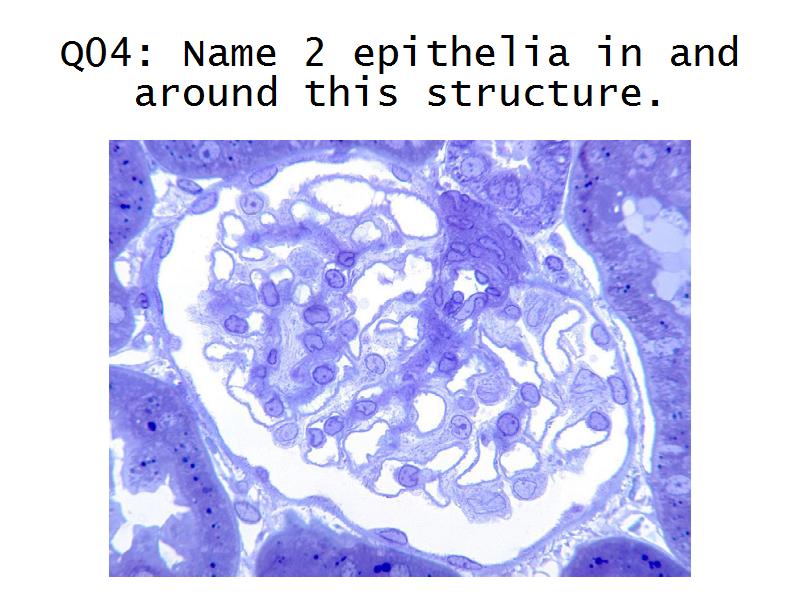

Kidney

Kidney

Slides 28 & 76

Kidney: Objectives

- Structure of the nephron and collecting tubules

- The renal corpuscle

- Make an annotated diagram of a nephron, including the juxtaglomerular apparatus. Indicate the flow of blood and water in each part, and how solutes are filtered, secreted and reabsorbed.